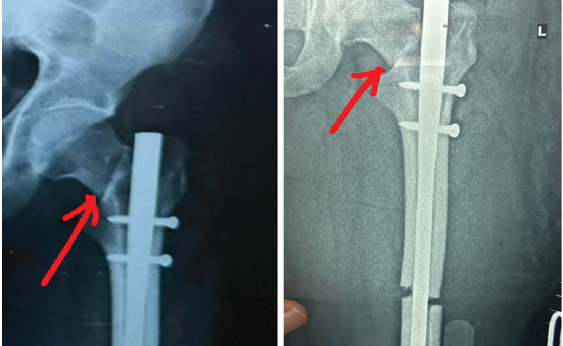

Post-operative X-ray was done, and it revealed a fracture of the neck of the femur. X-ray also revealed distraction at the fracture site (Fig. 2). Patient post-operative day 2 developed fever and respiratory distress and saturation 96% on room air, followed by which the patient referred to Goa Medical College, Bambolim, on June 17, 2025 in view of suspected fat embolism.

Figure 2: Immediate post-operative radiograph of the hip after the first surgery revealed iatrogenic neck femur fracture (marked with red arrow in figure 2) along with distraction at the shaft femur fracture site, which was not corrected after the first surgery.